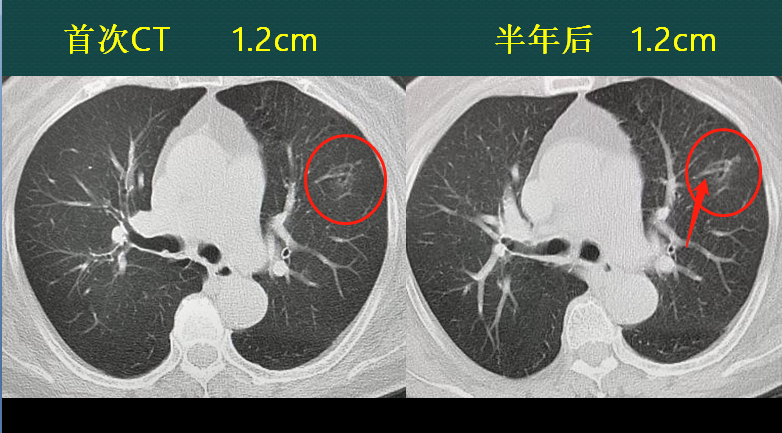

恶性肺结节,如果不重视ct定期复查,会发生什么?